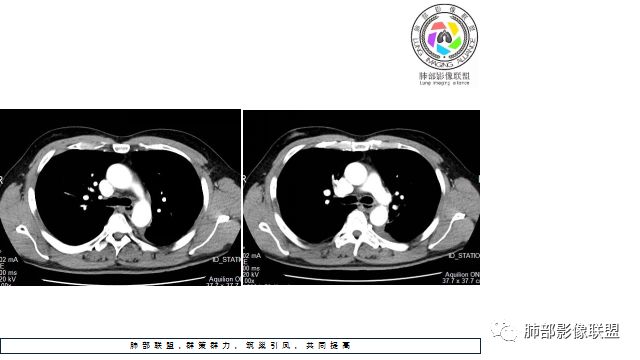

@罗冬楚-湘乡市第二人民医院放射科?我觉得还有一个层面支持小细胞;

罗老师您看看这个层面,有没有说明病灶比较软?

1.左下肺门区巨大肿块,支气管显示不清,轻度阻塞性炎症,没有明显肺不张,提示管腔受压狭窄可能性大于堵塞,这较少见于鳞癌。

4.病灶内有肺动脉走形,血管局部受压,未见破坏,病灶乏血供,呈血管包埋或血管造影征;侵袭性力强及破坏力弱、血管漂浮都符合SCLC,所以鳞癌的可能性也不大。

5.左肺门块影或淋巴结肿大,竭力挤兑肺门血管结构,呈冰冻肺门;有时候SCLC可以单独呈现冰冻肺门,而没有没有冰冻纵隔。